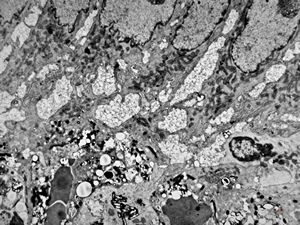

herpetic oesophagitis